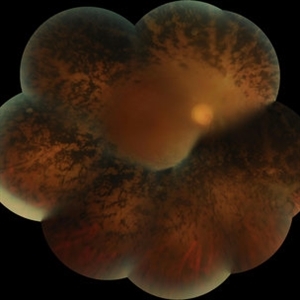

Best Disease Mar 9 2013 by Hamid Ahmadieh, MD Color fundus photograph the left eye of a 49-year-old man with decreased VA due to advanced Best disease. Photographer: Soodabeh Fooladin, Negah Eye Center, Tehran Condition/keywords: Best disease